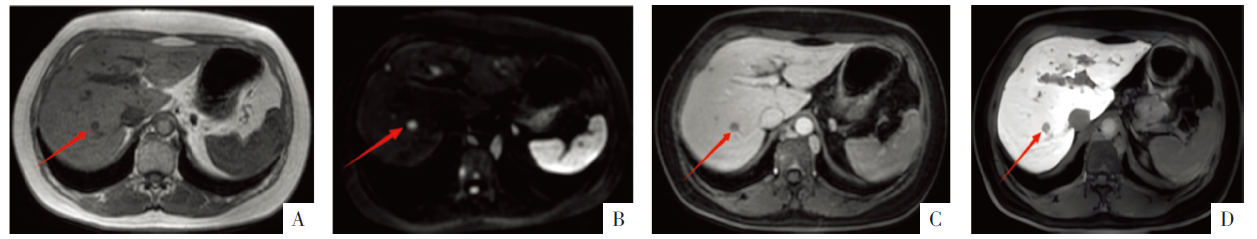

• 图3 胆囊病变的MRI影像。A—C图分别为T2WI、DWI、ADC图,D图为增强MRI静脉期影像。箭头示胆囊病灶。

• 图4 肝脏病变的MRI平扫及增强影像(以肝右后叶上段病灶为例)。A、B图分别为T1WI、DWI影像,C、D图分别为增强MRI移行期、肝胆期影像。箭头示胆囊病灶。